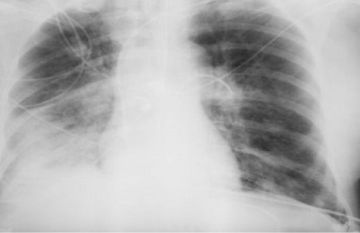

الوقائع الإخباري: أفادت الدكتورة أوكسانا بلاتونوفا، أخصائية الأشعة، أن الأشعة السينية لا تزال أداة تشخيصية مهمة، ولكن المخاوف حولها ما زالت قائمة.

وتقول: 'الأشعة السينية هي إشعاع كهرومغناطيسي، مثل الأشعة فوق البنفسجية والضوء والحرارة. صحيح قد تلحق جرعاتها العالية الضرر بالخلايا، كالذي تسببه حروق الشمس. وأن الاستلقاء تحت أشعة الشمس على الشاطئ دون حماية أخطر بكثير من تصوير بالأشعة السينية للصدر مرة واحدة سنويًا'.